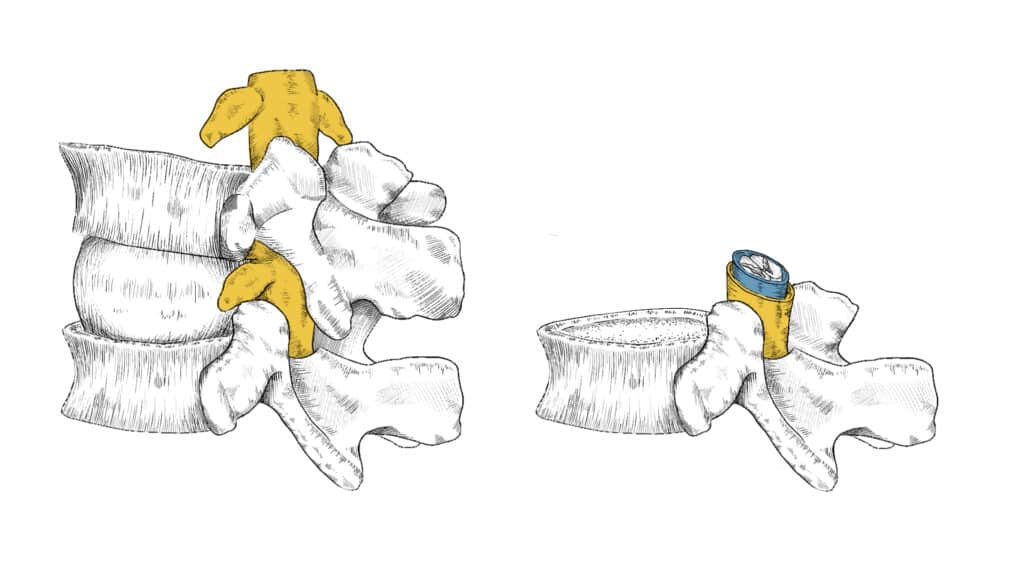

Przestrzeń nadtwardówkowa, inaczej opisywana jako przestrzeń zewnątrzoponowa, to obszar otaczający rdzeń kręgowy i nerwy, znajdujący się pomiędzy oponą twardą (najbardziej zewnętrzną warstwą opon mózgowo-rdzeniowych) a kanałem kręgowym. Podanie leku do tej przestrzeni umożliwia dotarcie leku bezpośrednio do źródła bólu, czyli w okolice nerwów oraz zmian powodujących ucisk na nerwy, takich jak wypuklina lub przepuklina krążka międzykręgowego, zmiany zwyrodnieniowe lub ciasnota kanału kręgowego. Precyzyjne podanie leków w okolice kręgosłupa pod kontrolą fluoroskopii, czyli rentgena śródoperacyjnego, to jedna z najbardziej precyzyjnych, a przez to bezpiecznych technik zwalczania zespołów bólowych kręgosłupa. W ramach Szpitala Klinicznego im. W. Degi technika ta została wprowadzona przez dr. Kubaszewskiego w 2004 roku. Zebrane doświadczenie pozwala na najbardziej optymalne zaplanowanie i przeprowadzenie leczenia.

Podanie leku do przestrzeni nadtwardówkowej jest wykonywane przez lekarza specjalistę (najczęściej anestezjologa lub neurochirurga) w warunkach ambulatoryjnych (pacjent wraca do domu tego samego dnia). Zabieg polega na wprowadzeniu igły do przestrzeni nadtwardówkowej pod kontrolą RTG (fluoroskopii), co zapewnia precyzyjne dotarcie do celu. Następnie podawany jest lek, którym najczęściej jest mieszanina kortykosteroidu (działanie przeciwzapalne) i środka znieczulającego miejscowo.